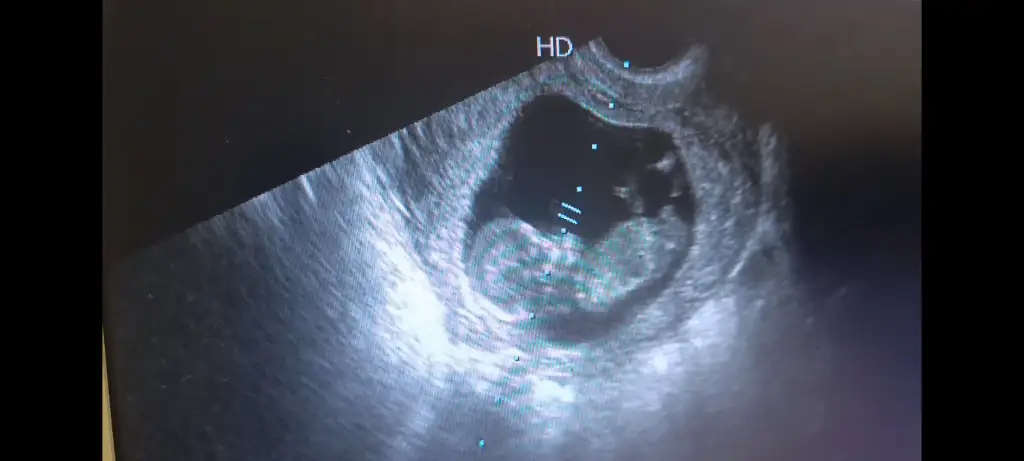

Benimde 7 aydır sağ tarafim da batma vardı. Her ay hissediyordum. Gebelikte te de ara ara hissetmeye devam ettim. Muhtemelen büyük bir kistim vardı. Doktorlar bir şey demedi ama sürekli aynı yerde hissettiğim için diyorum. Geçen gün çocuklarla uğraşırken biraz zorlandım. O sıra o batan yer biraz daha ağrıdı. Peşinden hafif kahverengi akıntı geldi. O günden beri batma hissi kayboldu. Sanırım o gün kistim patladı. Allahu alem.Hanımlar benim sürekli sol kasigim ağrıyor batma şeklinde gebeliğin başından beri ağrısı bazen sol bacağıma vuruyor sizde de tek taraflı kasik ağrıları oluyor mu . Bende ayrıca çikolata kistim var ondan mi kaynaklı yoksa gebeliğin belirtilerinden mi bu .